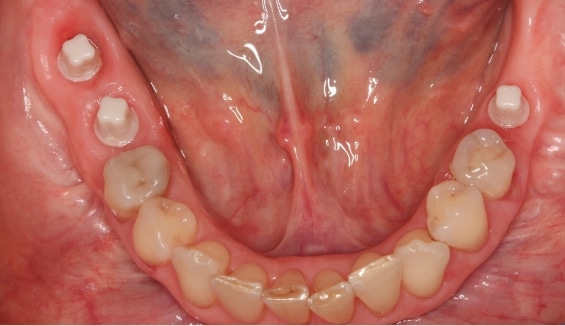

For a specific group of patients, ceramic dental implants in Boston signify a groundbreaking evolution in dental implant technology, offering almost a complete metal-free, aesthetically pleasing, and biocompatible option for tooth replacement. These implants serve as an alternative to traditional titanium dental implants, crafted from high-strength, biocompatible ceramic material known for its durability and natural appearance.

Versatile in their applications, ceramic implants can be used for single-tooth replacement, multiple teeth, or full arch restorations, catering to various dental needs. Beyond aesthetics, they provide stable support for dental restorations, allowing patients to eat, speak, and smile with confidence and comfort.